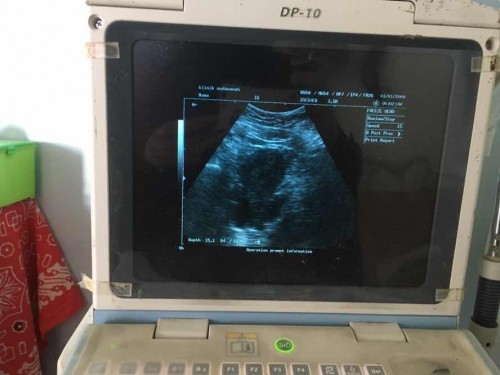

Ada yang pernah ngalamin ndak bun, usia kehamilan udah 9mnggu mnurut hpht tpi di usg belum kelihatan janinnya?

Worry bgt bun, takut kenapa”